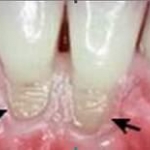

- Fluor là chất được một số quốc gia bổ sung vào nước sinh hoạt nhằm chống sâu răng. Vào thập niên 40 ở Mỹ đã có những cuộc điều tra và đã kết luận, fluor là chất chống được sâu răng ở liều lượng nhất định. Nếu nồng độ fluor trong nước vượt quá 1,5mg/l sẽ dẫn tới bệnh đốm và giòn răng. Ở nồng độ 1mg/l chống sâu răng là tốt nhất. Nồng độ này giảm cũng dẫn tới gia tăng bệnh răng miệng. Tổ chức Y tế thế giới đã kết luận: Nếu bổ sung nồng độ fluor vào nước uống cao hơn 0,6mg/l sẽ làm hạn chế những bệnh về răng ở trẻ em và khoảng tối ưu phải có 1mg/l. Ở nghiên cứu khác còn cho thấy nó có thể làm giảm quá trình xơ cứng động mạch của người già, bổ sung canxi cho trẻ nhỏ. Vì lí do đó, trên thế giới có trên 250 triệu người dùng nước sinh hoạt được bổ sung chất fluor. Ở Mỹ trên một nửa dân số dùng nước sinh hoạt cũng được bổ sung chất này.

- PGS.TS Lê Văn Cát, Viện hóa học Công nghệ Việt Nam cho biết: fluor trong nước uống là hợp chất fluor vô cơ xâm nhập vào cơ thể giúp làm cứng men răng. Từ nhiều năm nay, tận dụng những ưu điểm của fluor mà người ta đã dùng nó để chế ra kem đánh răng với hàm lượng nhỏ hơn 1,5 mg để bảo vệ răng.